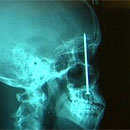

![]() Just imagine what kind of crazy shit is stuck in your body.